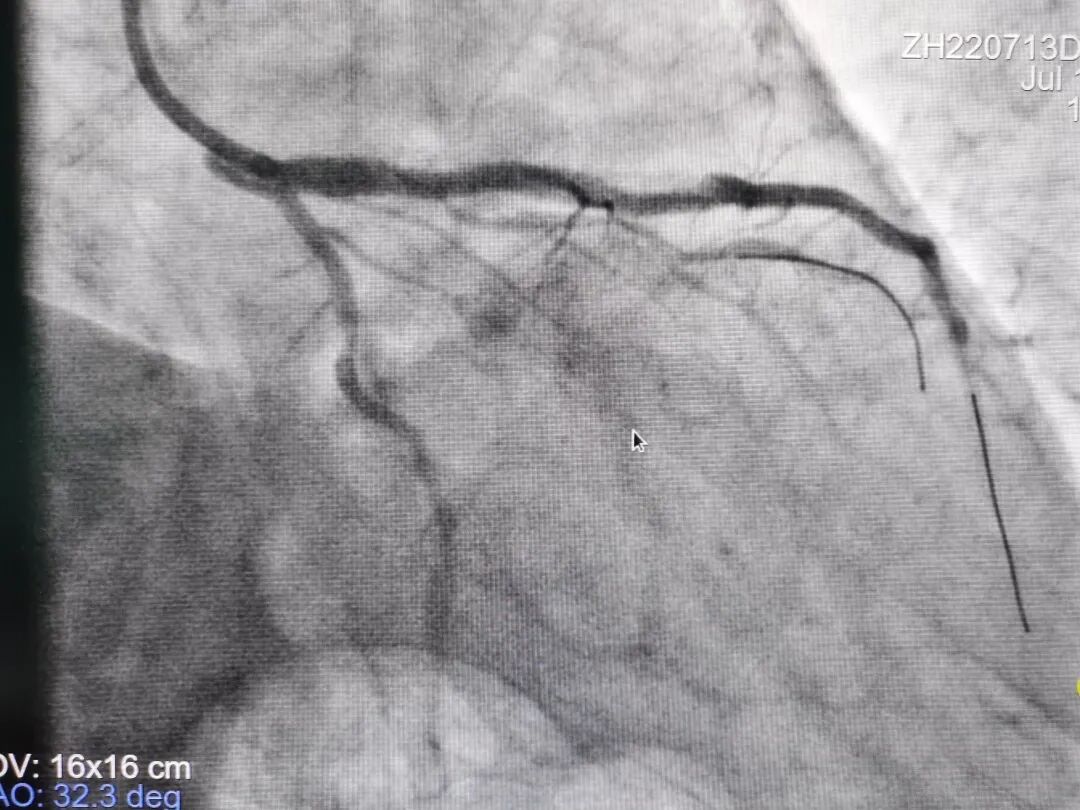

术后影像

据心内科廉哲勋主任介绍,病人是一位62岁的男性冠心病患者,外院造影显示冠状动脉左前降支近中段有弥漫、严重狭窄伴重度钙化及血管迂曲,从外院转入青大附院。经团队充分讨论后,在血管内超声评估和指导下,采用Shockwave冲击波球囊钙化斑块碎裂技术,精确冲击冠状动脉内膜和中膜下钙化病灶后,顺利植入支架。